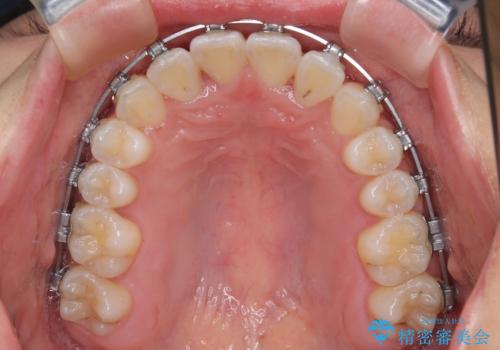

- 矯正装置

- メタルブラケット

ワイヤー矯正でもマウスピース矯正でも対応可能でしたが、マウスピースによる自己管理に一切の自信がないとのことで、ワイヤー装置にて矯正治療を行うこととしました。

装置の外見を気にしていましたが、短期間で治療を終えることができるだろうと伝えると、安価であるメタルブラケットを選択されました。

想定通り、1年強で綺麗に仕上げることができました。